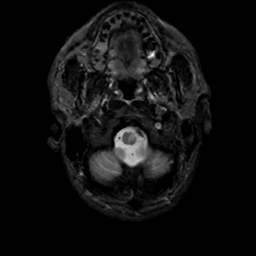

MR Study #12, May 12, 1991 -- Slice #3

[Home][Help][Clinical][Tour 1][Tour 2] Slice 3